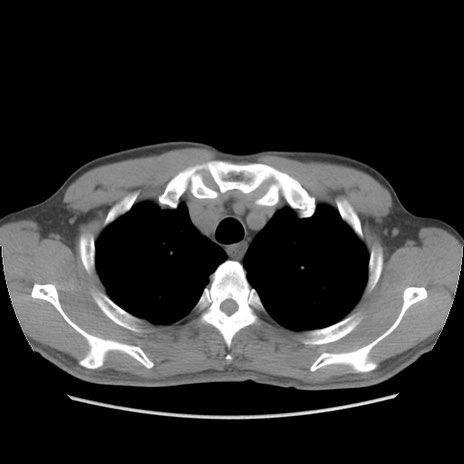

症例56 CT(横断像)

脂肪ウインドウ